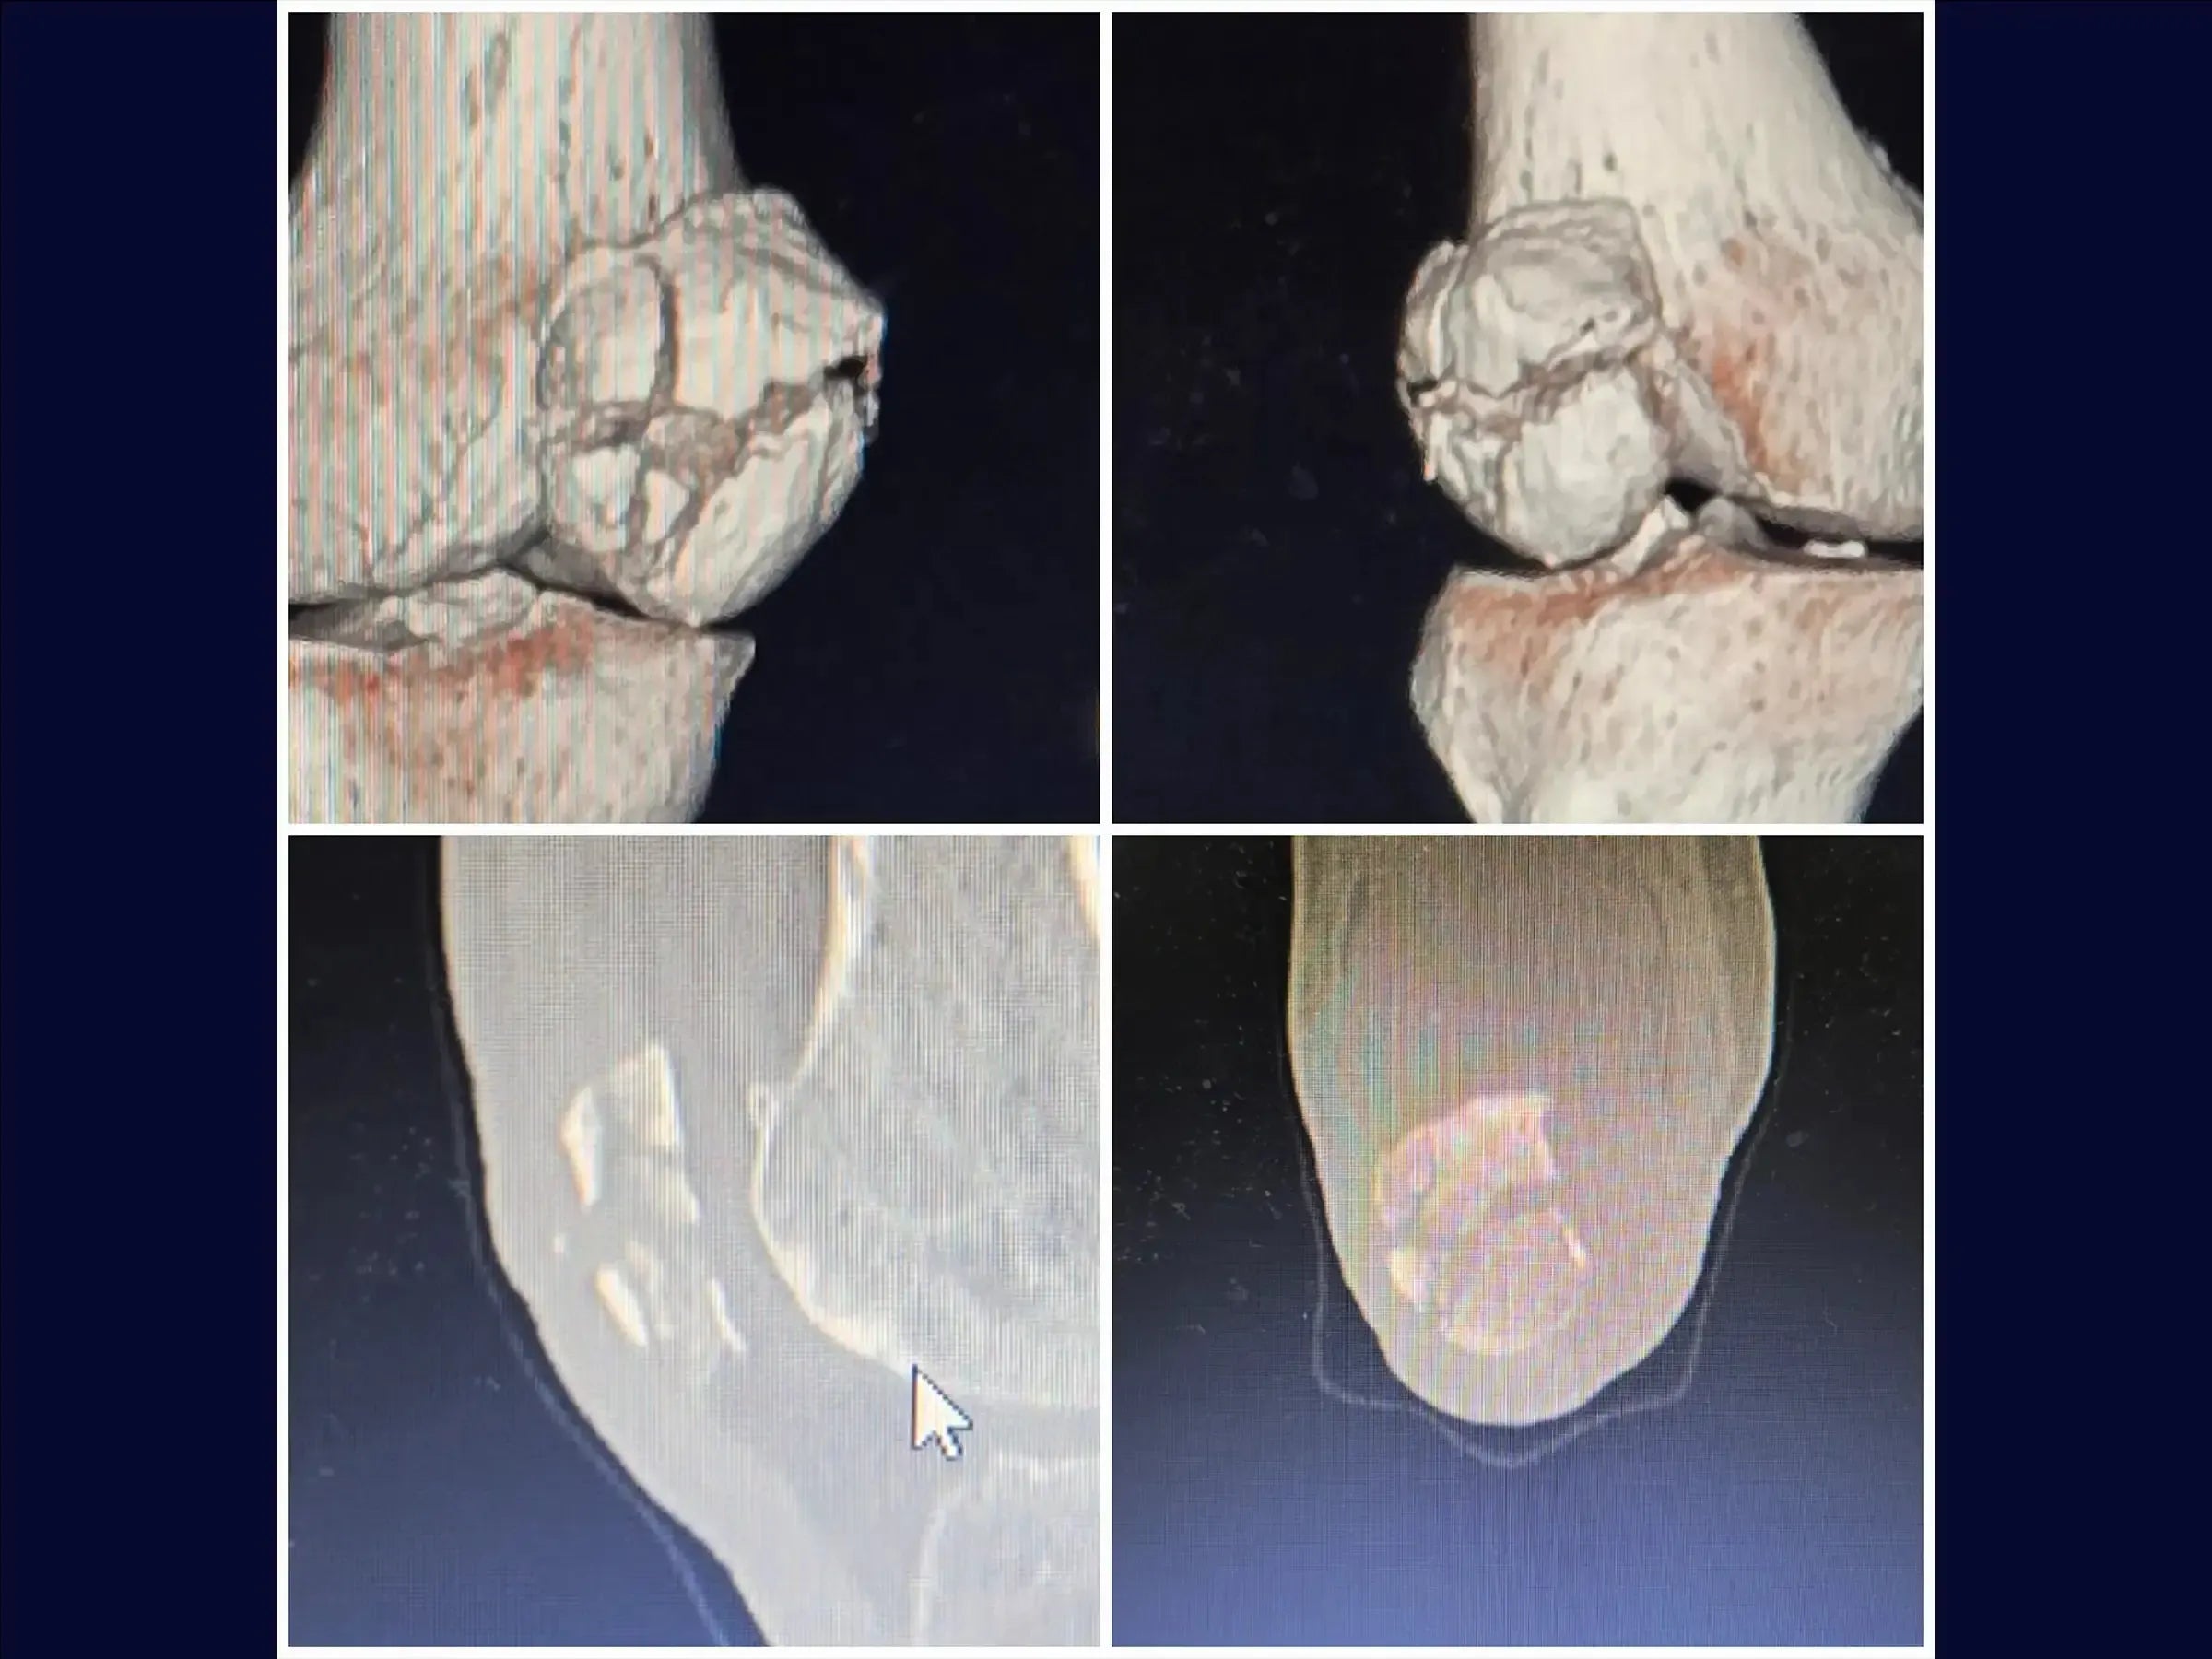

O manejo de fraturas multifragmentares da patela com comprometimento do mecanismo extensor representa um desafio técnico significativo na ortopedia. Este treinamento oferece uma imersão prática na osteossíntese que restaura a congruência articular e a função extensora, minimizando a proeminência do material.

- Tratamento cirúrgico de fraturas multifragmentares da patela com comprometimento do mecanismo extensor.

- Redução anatômica e fixação estável.

- Acesso Cirúrgico Otimizado: Demarcação precisa e incisão única para manipular fragmentos intraoperatoriamente e identificar "dentes" da fratura, facilitando a redução.

- Técnica de Redução Precisa: Metodologia para utilizar a pinça de redução e a mão como molde, ajustando a ancoragem para estabilidade primária sem translação.

- Identificação do Fragmento Chave: Foco na importância do polo inferior inserido ao tendão patelar como ponto crucial para a redução e concentração de parafusos com arruela para estabilização.